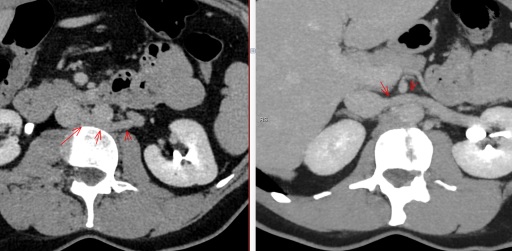

Veine rénale gauche circum-aortique

Veine renale circumaortique

Veine renale circumaortique